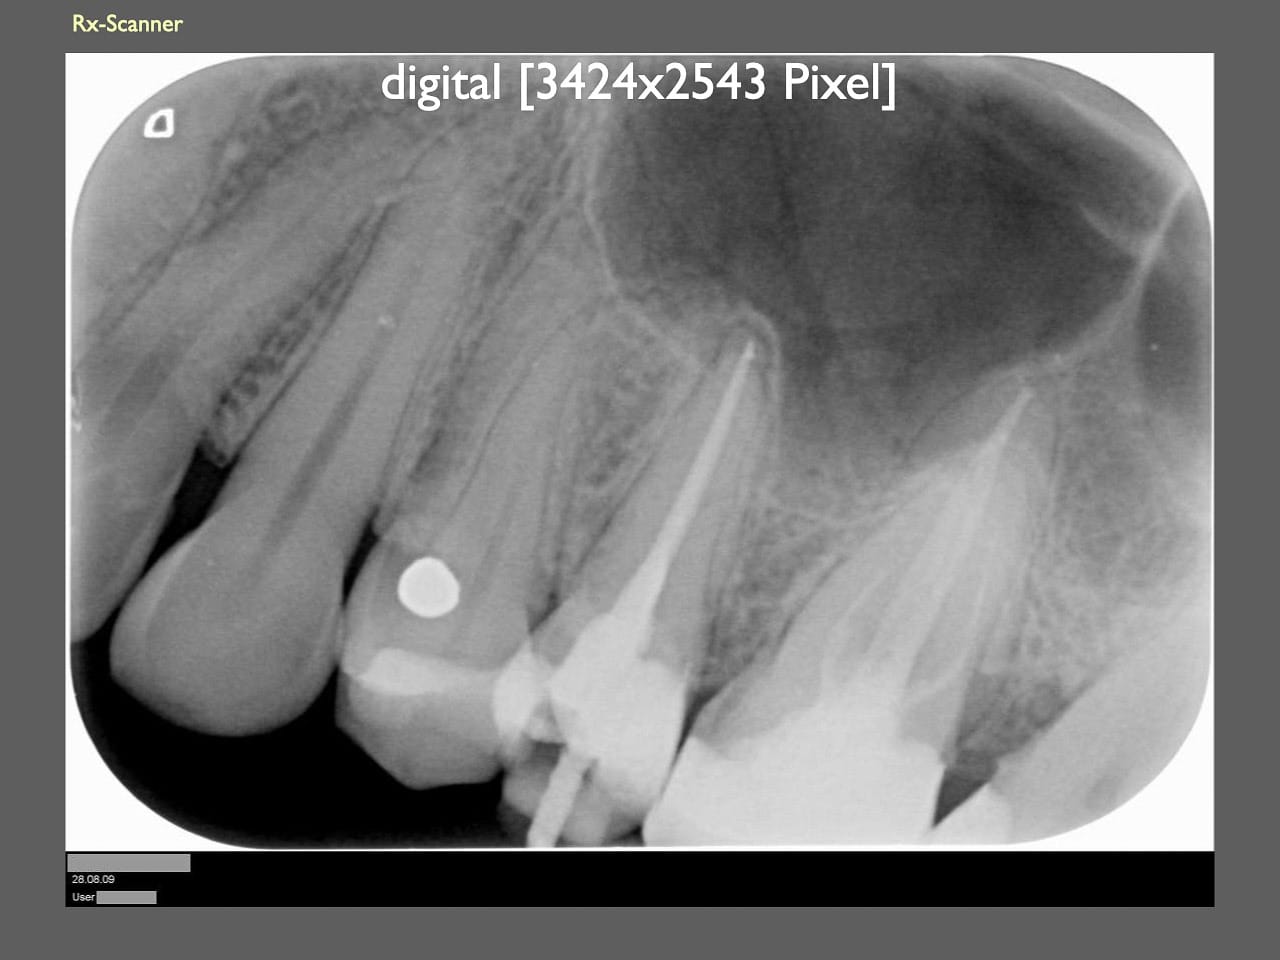

dental Scannen in der Zahnarztpraxis. Study Club vom 28.2.2010. Von peter portmann, Veröffentlicht am 28. Feb. 2010 — 3 min Lesezeit dokumentationfoto Auf dieser Seite Zahnarztpraxis-Trilogie zu Fotografie und Dokumentation Portrait Fotografie Scannen Scannen